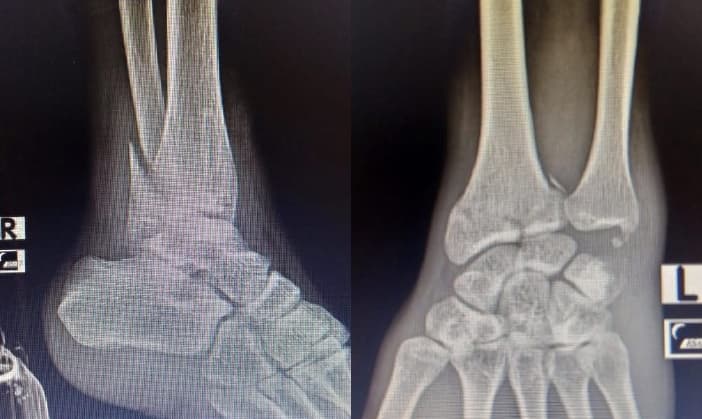

Long story short, I experienced a motorcycle accident in mid-2021 that resulted in broken bones in my right ankle and left wrist.

Recovery lasted for 9 months, during which time I had difficulty walking and typing.